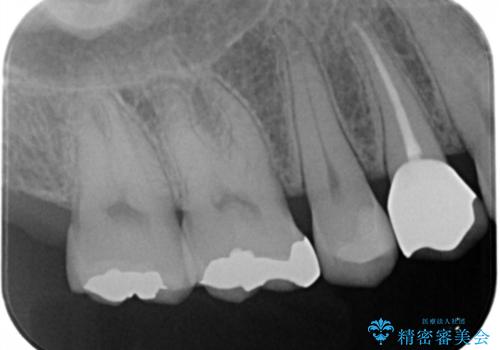

拡大鏡下で虫歯を全て除去しゴールドインレーにて治療しました。

- ゴールドインレー 7.7万円費用は治療当時の料金となります

ゴールドインレーはメタルインレーに比べて、歯と詰め物の隙間が生じにくため

虫歯菌が侵入することなく、虫歯の再発のリスクが低いです。